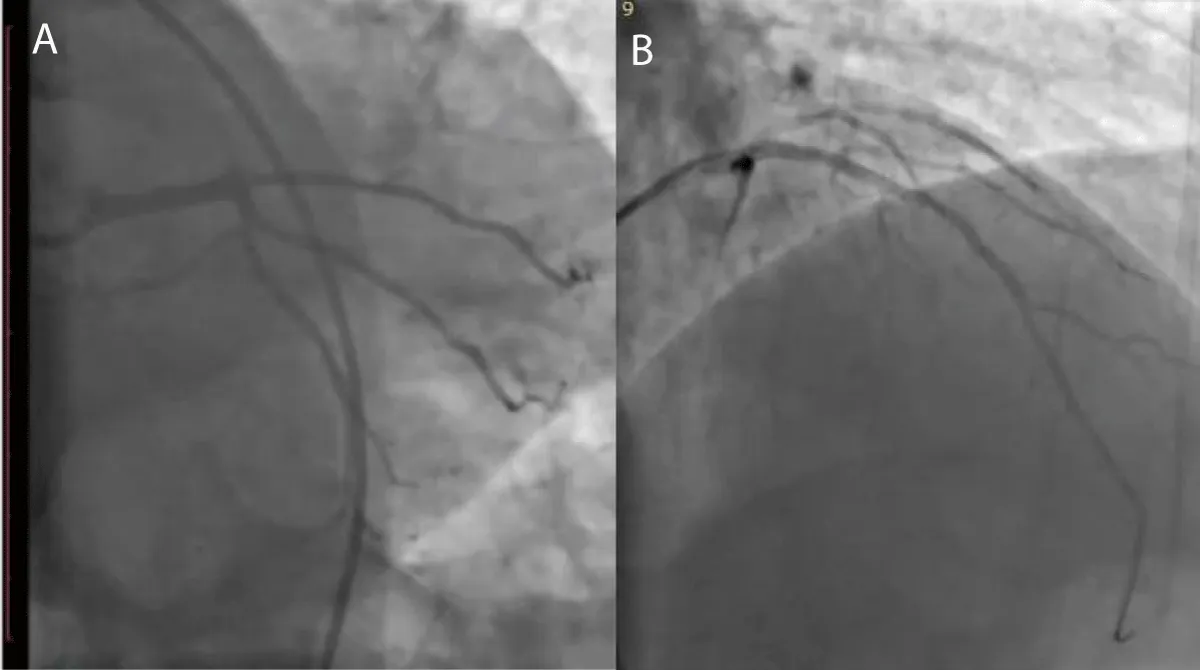

A 63-year-old male patient, previously healthy, hypertensive, diabetic and heavy smoker presented with acute burning chest pain radiating to both shoulders, which was associated with sweating and vomiting for 1 hour, but during hospitalization in the emergency room, he developed sudden onset of altered level of consciousness, dysarthria, nystagmus with National Institute of Health Scale Score (NIHS) score 12, after discussing the case we planned to do coronary and cerebral angiography. On examination the patient looks in pain, sweaty and tachypneic, and their blood pressure: was 75/40 mmHg, Electrocardiography was done and it revealed ST segment elevation in the anterior leads with ST-segment depression in I, II, AVF after that he received 300 mg of aspirin, 300 mg clopidogrel and norepinephrine 3 mcg/kg/min intravenous was started and urgently he was transferred to cardiac catheterization department for primary Percutaneous Coronary Intervention (PCI). During coronary angiography, it showed total occlusion of the proximal left anterior descending artery, stenting was done successfully by using resolute integrity 2.75 x 22 mm drug-eluting stent (Figure 2), then cerebral angiography showed normal anterior and middle cerebral circulation, but there was severe right vertebral artery stenosis, so angioplasty to vertebral artery was planned and it was done successfully (Figure 3), echocardiography was done and it showed reduced left ventricular Ejection Fraction about 30% - 35%, but no left ventricular thrombus was detected, then the patient was followed for 3 days at the hospital and he was discharged on Dual antiplatelet and he had mRS (0) with regular follow up at the outpatient clinic for 3 months, he had the good general condition and functioning well without any neurological deficit mRS (0).

Figure 2: A-coronary angiography shows proximal LAD total occlusion, B-after stent implantation in ostial LAD.

Figure 3: A- Cerebral angiography shows severe right vertebral artery stenosis, B- After successful angioplasty for vertebral artery.